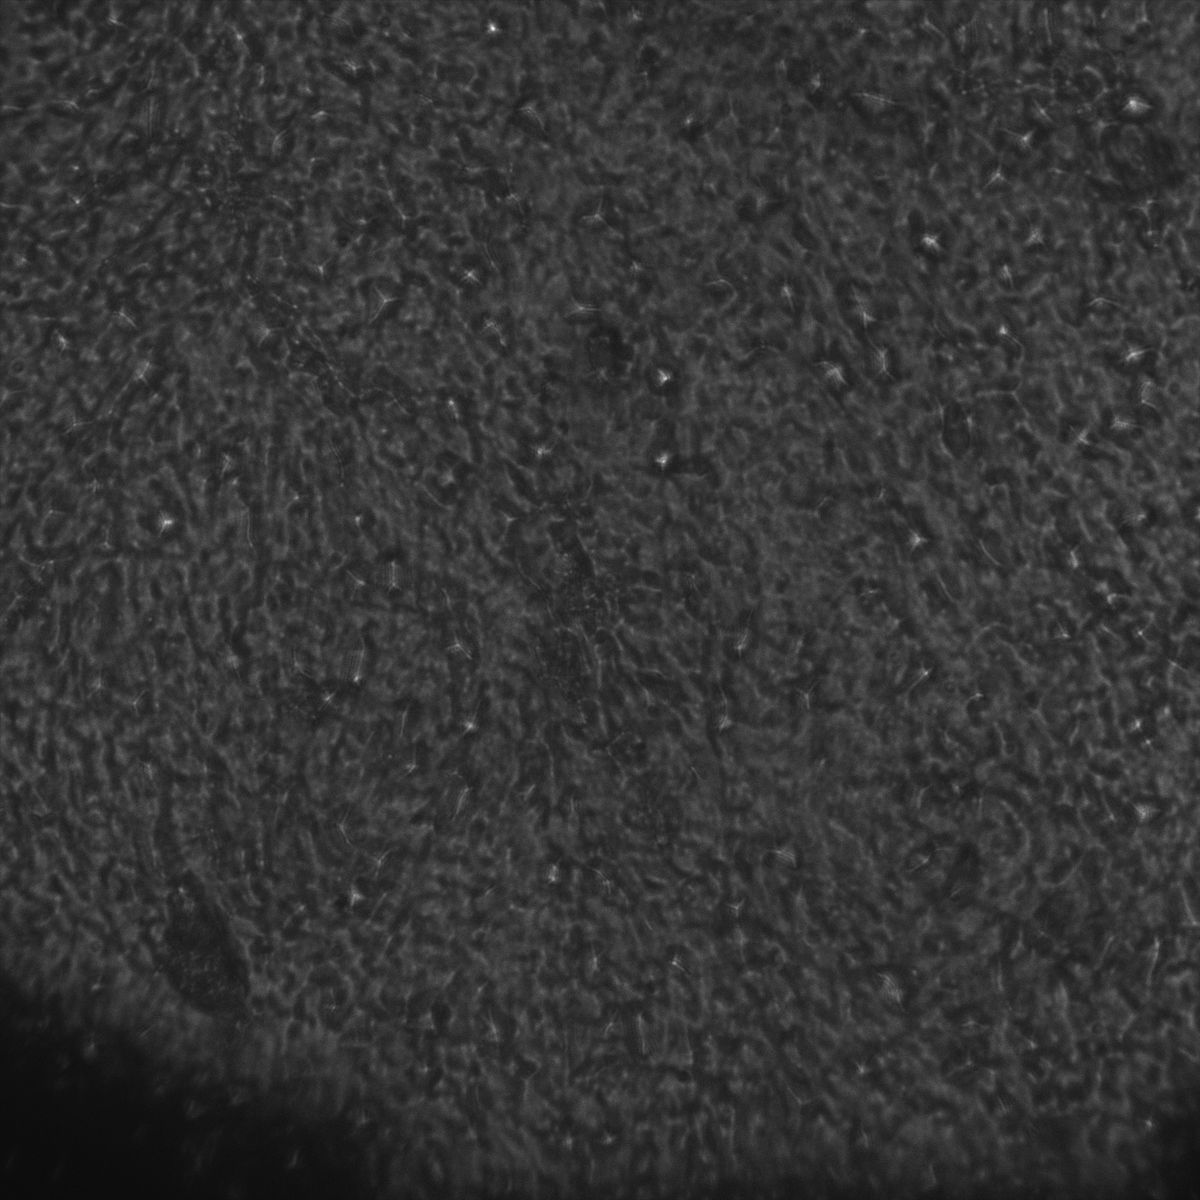

Tubulin

Tubulin - Bip

Tubulin - Nuc